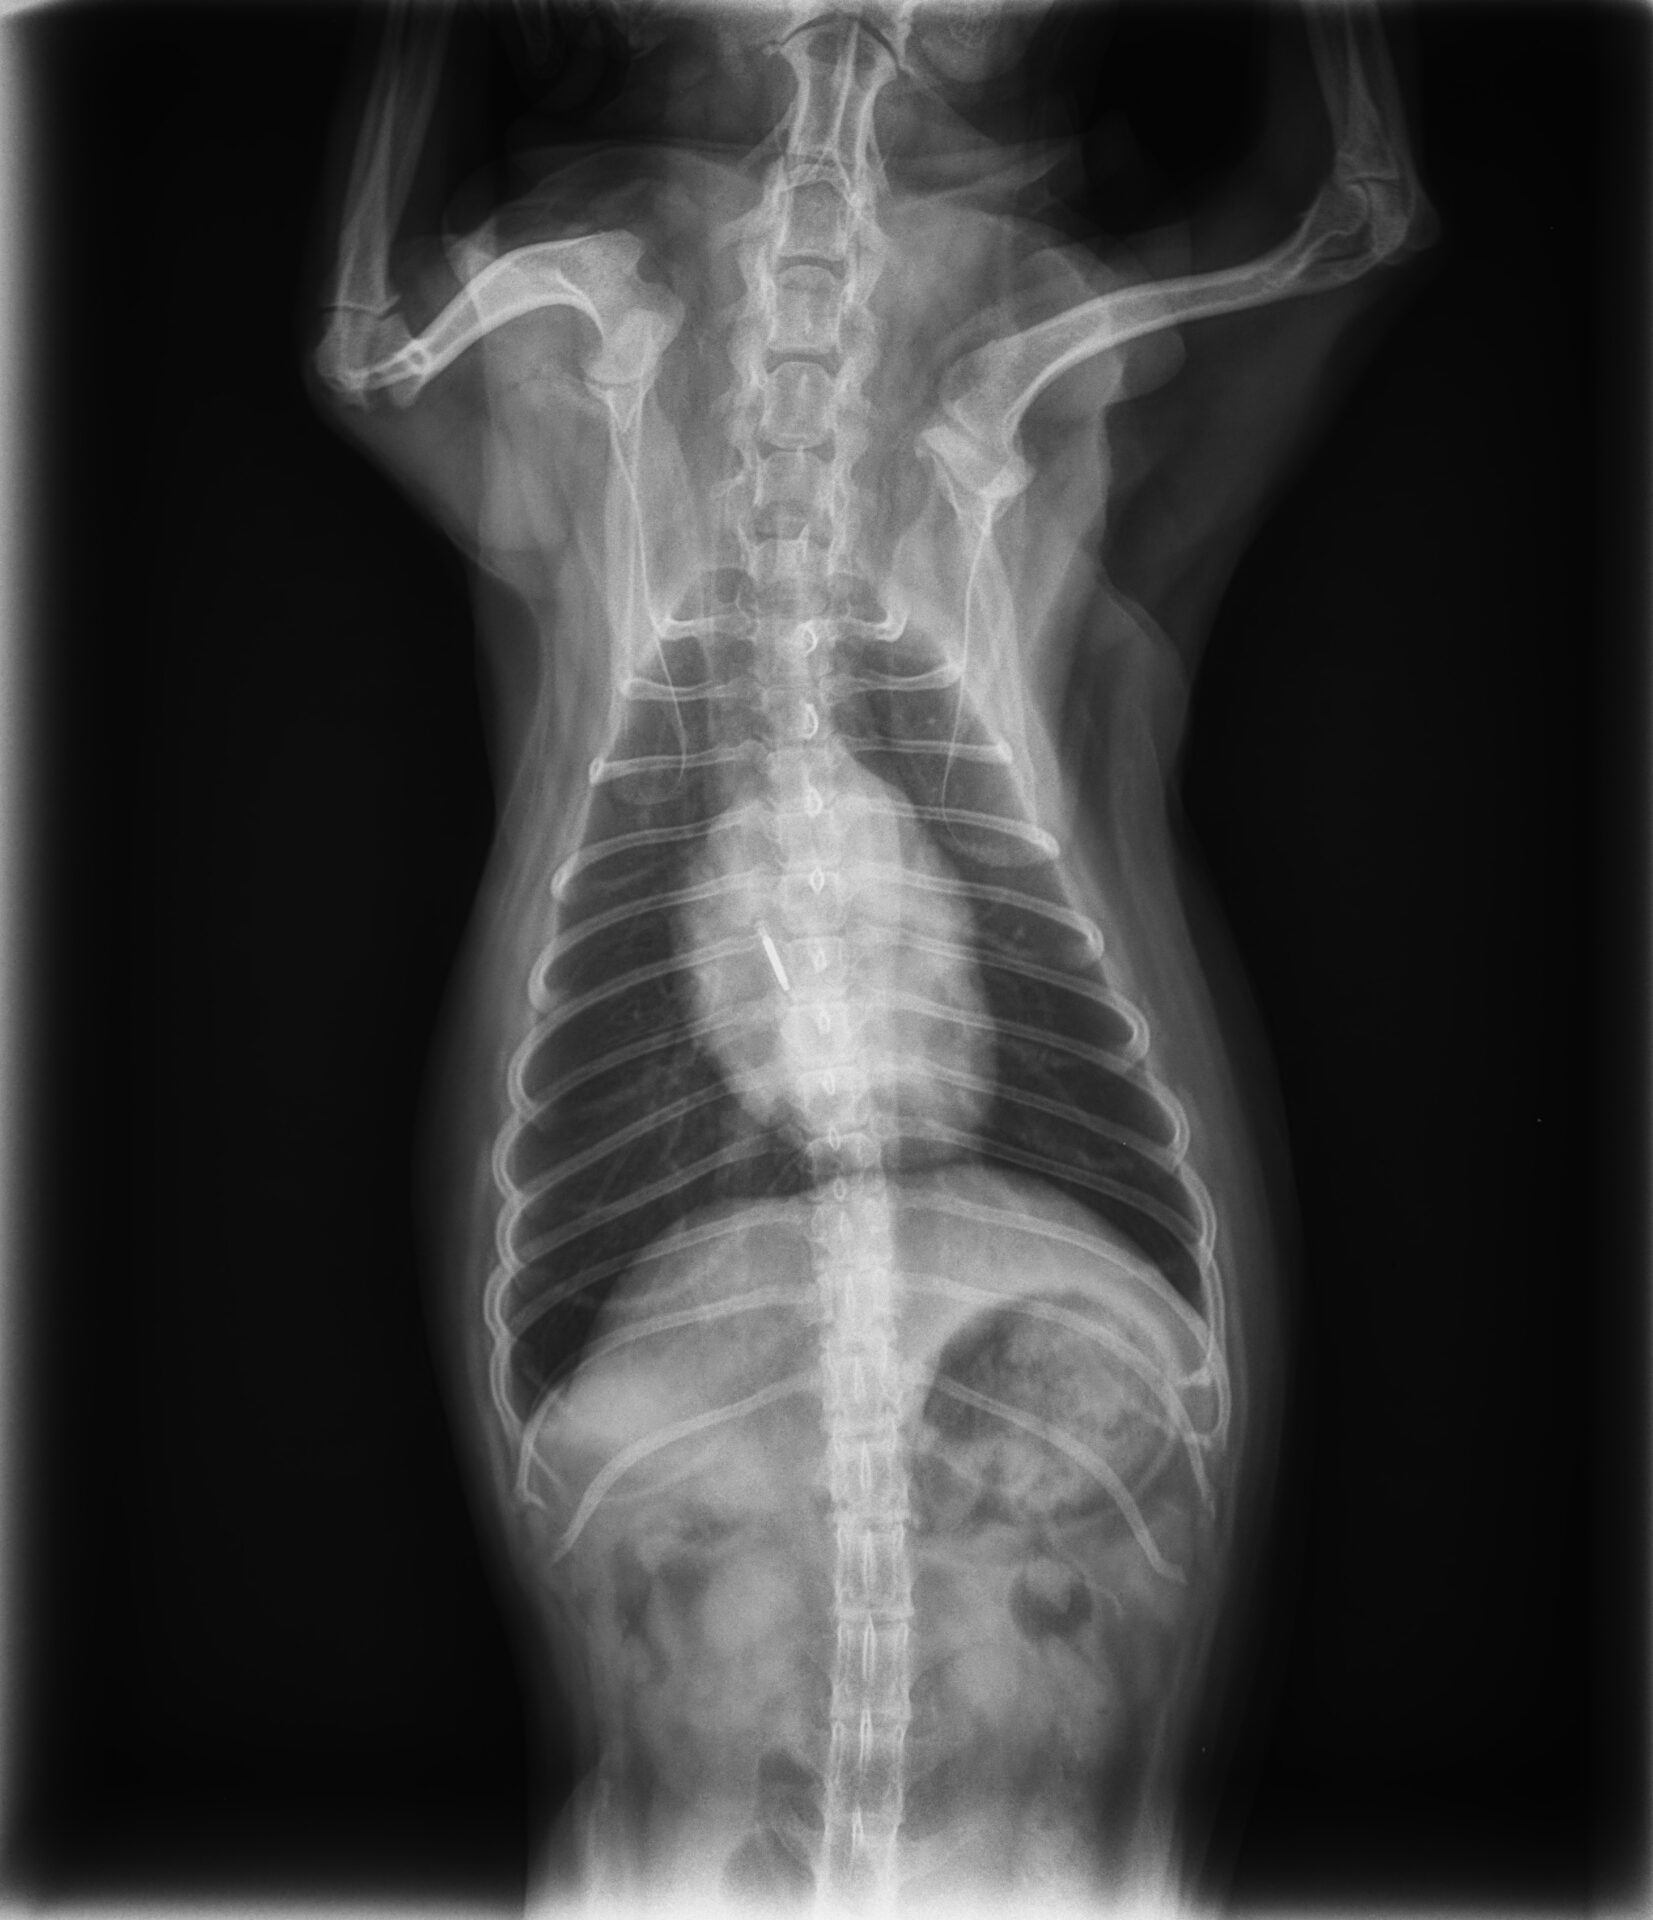

B2:心臓拡大あり→B2では症状がなくとも心不全リスクを軽減するために投薬治療を始めることが推奨されています。心拡大と症状の発症を遅らせることが投薬の目的となります。

画像は心臓の拡大傾向を認めますが特に症状は見られない状態でした。